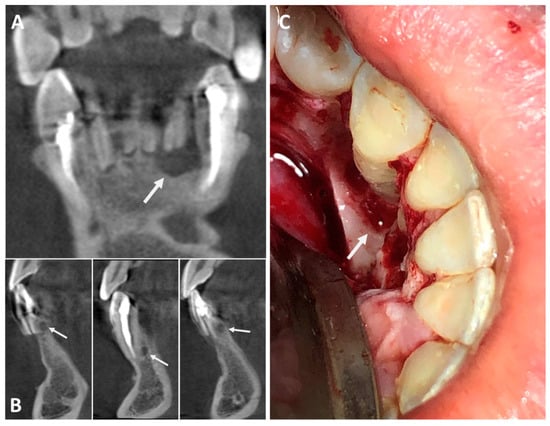

The histopathological examination showed multiple cysts lined by stratified epithelium with varying thicknesses and characteristics. The cystic lining was characterized partially by a flat squamous stratified epithelium with areas of thickening and partially by a cuboidal epithelium, evidencing foci of hobnail cells. Clear cells and mucous cells were present, in addition to duct-like structures, which were filled with eosinophilic amorphous material that was positive for periodic acid–Schiff (PAS) staining after diastase digestion. The cyst wall was composed of dense connective tissue and a mild diffuse chronic inflammatory infiltrate (Figure 2). Based on these characteristics, the diagnosis of GOC was established.

Figure 2. Photomicrographs of the histopathological analysis, detailing the morphological features. (A)—Hematoxylin and eosin (H&E) staining: Thin connective tissue capsule lined by stratified epithelium that is partly squamous (black arrow), partly cuboidal (green arrow). The epithelium also presented areas of thickening and papillary projections towards the lumen (100× in the original). Inset shows the presence of mucous cells and duct-like structures (yellow arrows) (400×). (B)—PAS-diastase staining evidenced hobnail cells (red arrow) on the epithelial surface and mucin-filled intra-epithelial duct-like structures (blue arrow).